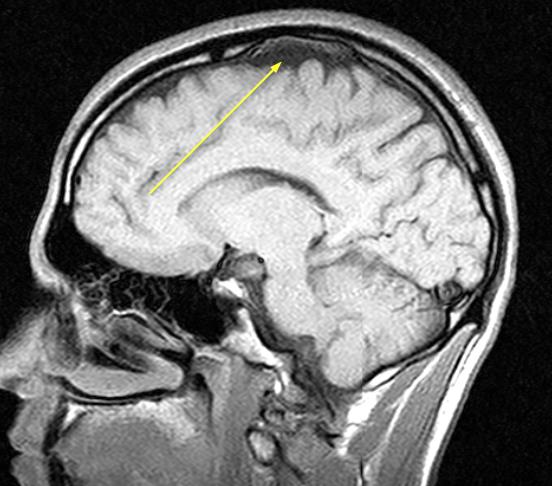

Медицинские аспекты и диагностика субдуральной гигромы мозга